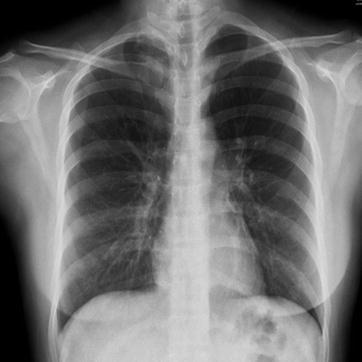

Fig. 23.5.

Adult measles pneumonia. X-ray demonstrates diffuse ground-glass opacity at both lungs